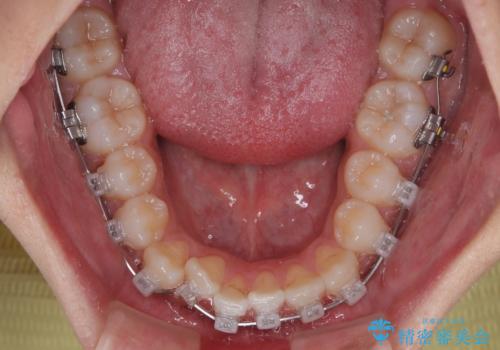

- クリアブラケット

- 「上下の前歯がガタガタしているのが気になる」とのことで来院された患者様です。

上下顎前歯部に叢生(歯の重なり・ガタつき)を認め、見た目だけでなく、歯磨きのしにくさも気にされて来院されました。